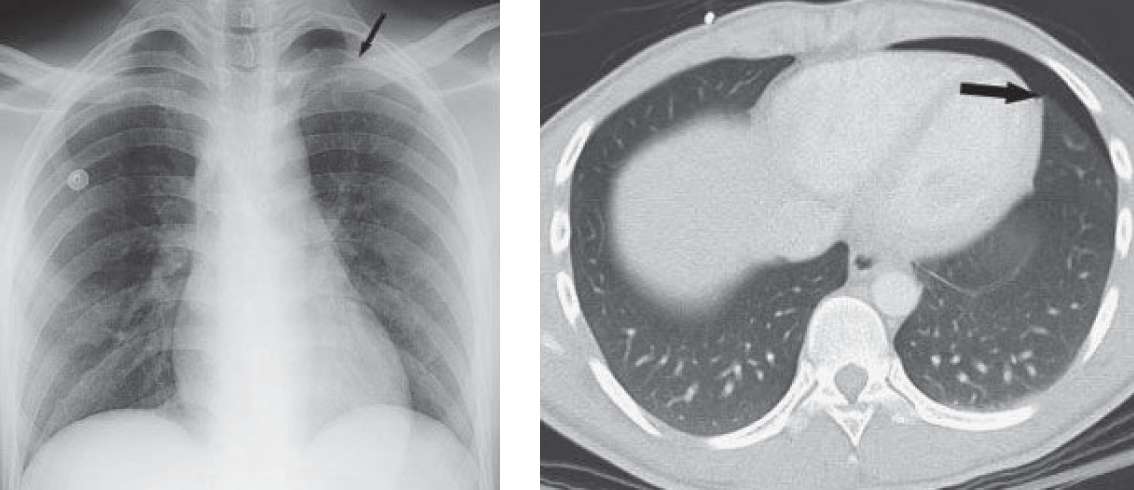

- Supine radiograph shows increased lucency at the left base, but no pleural line is seen. The left costophrenic sulcus extends more inferiorly than the right. Wires represent ECG leads overlying the patient.

- Follow-up abdominal CT (performed because of the history of trauma) and upright radiograph confirm the small pneumothorax (black arrows).

Follow-up abdominal CT (performed because of the history of trauma) and upright radiograph confirm the small pneumothorax (black arrows).